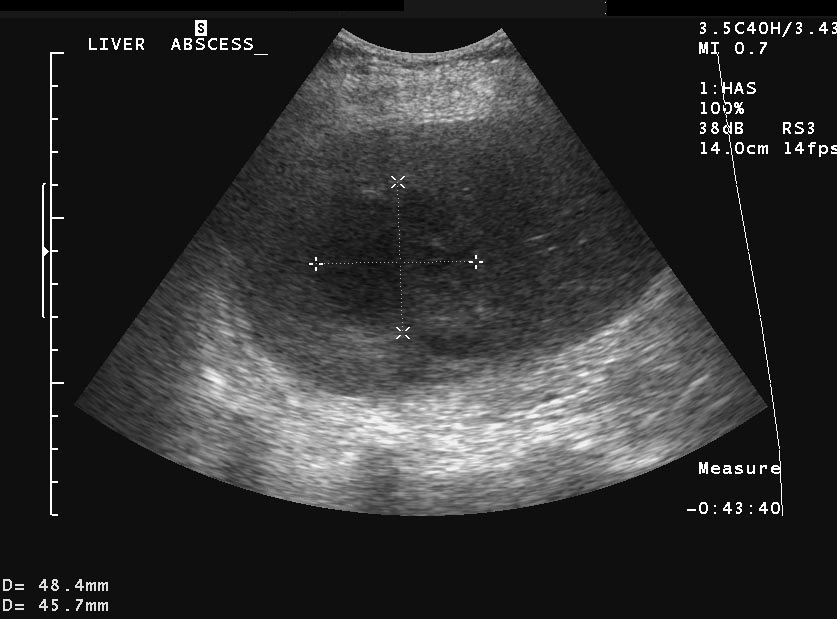

The bacteria may pile up in the biliary ducts due to the bile stasis (either by tumorous or inflammatory choledochus compression) and cholangitis can develop, associated with an abscess development later (Figure 29).

Figure 29: Abscess in the liver, US

Liver abscess can develop either following the severe inflammation of the biliary ducts and the gallbladder or following a tumorous necrosis or by the spread of an external inflammation to the liver. By the help of the US, a cystic lesion can be seen with multiple internal echos containing gas bubble frequently as well. In order to determinate the further therapy, contrast enhanced CT examination can be needed, if the US imaging of the entire liver was not possible. An avascular intrahepatic lesion can be seen well on the CT with a contrast enhancing wall (sometimes multifocal as well) (Figure 30). An US or CT guided percutaneous drainage can provide a therapeutic result depending on the lesion's size and location (Figure 31).

Figure 31: Abscess in the liver, US control after US guided drainage